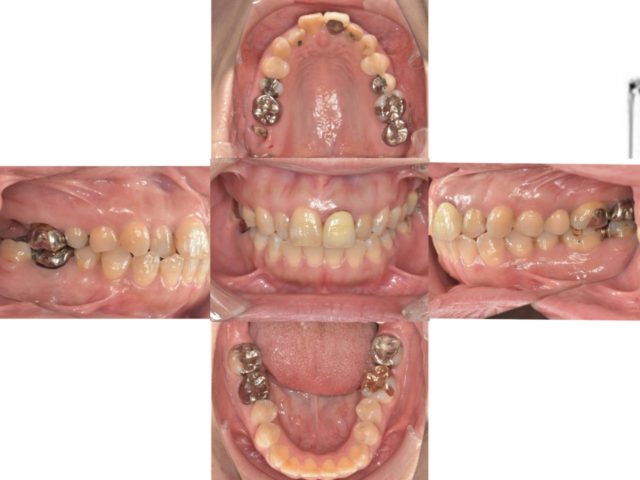

こちらが初診時の口腔内写真です。

“右上の1番奥の歯を他院で抜歯と診断されだが残したい”という主訴で来院されました。

検査診断の結果、この歯は抜歯でIPを行うことになりました。

歯を保存するためには歯茎から2mm以上歯が出ていること(フェルールの獲得)が条件となります。

今回のケースは歯に歯茎が乗ってきているので、歯茎を切って下げることで歯を出す処置(歯冠長延長術)が必要です。

しかし歯茎がかなり覆い被さってるので、フェルールを獲得するためには7mm歯茎を切って下げないといけないのですが、そうなると歯の根っこが露出してしまうため、保存不可能という診断です。